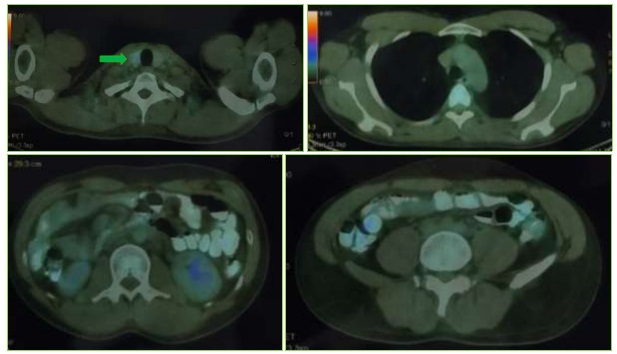

PET/CT sau điều trị:

Hình 5: Vài hạch nhỏ dọc phía trong cơ ức đòn chũm phải, không tăng chuyển hóa FDG. Thùy phải tuyến giáp cực dưới có nhân giảm tỷ trọng, trong có các nốt vôi hóa, tăng nhẹ chuyển hóa FDG (SUVmax: 2,84 (mũi tên xanh lá cây). Không thấy tăng hấp thu FDG tại các cơ quan bộ phận khác của cơ thể.